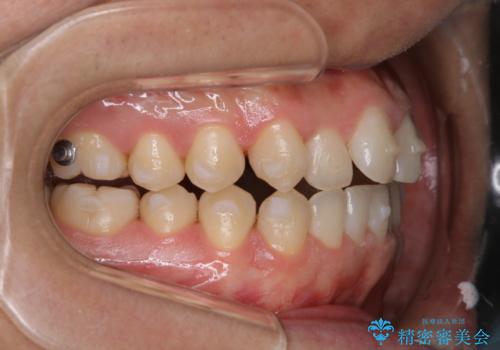

インビザラインで矯正治療中のクリーニング(PMTC)

- 全体的にクリーニングしてほしいとのことで来院されました。

PMTC60分コースを行いました。

インビザラインでの矯正治療は、歯の表面にアタッチメントといって白い突起を付けますので、材料の質的にも普段よりも汚れがかなり付着します。着色も付きやすいです。

虫歯や歯周病が進行しないように定期的にクリーニングすることをおすすめします。インビザライン経過のチェックが2、3ヶ月に1回のためそのくらいのペースで一緒にクリーニング行うことが最適です。